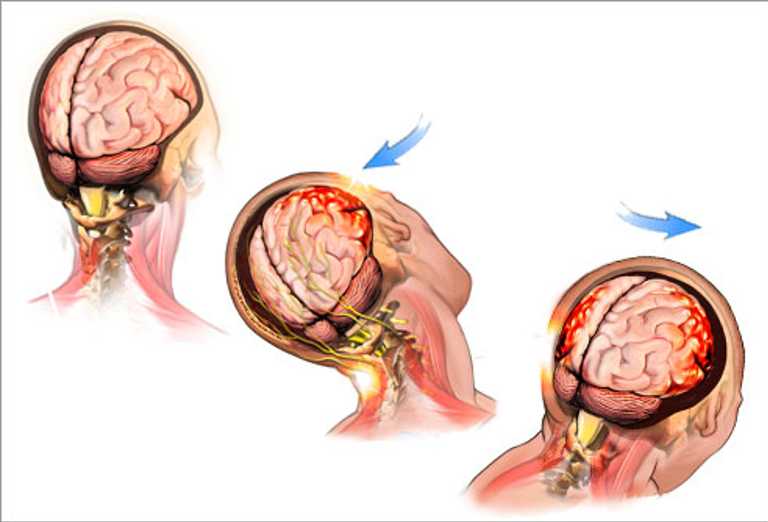

Many individuals don’t realize that a concussion can occur without even hitting the head, such as in the case of a car accident in which a sudden stop can cause the brain to hit the inside of the skull. In some cases, the symptoms resulting from such injuries are also attributed to other culprits or given other diagnoses.

drawings of brains with direction of injury causing concussion